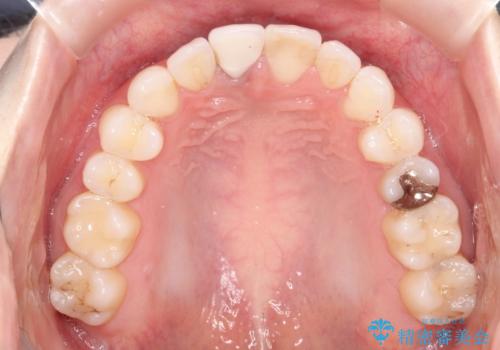

- 前歯の凸凹を主訴に来院されました。

インビザラインにて短期間で満足いく結果が得られたと大変喜ばれました。

歯と歯の間に僅かなスペースを作って配列していました。追加アライナーを1回行っています。